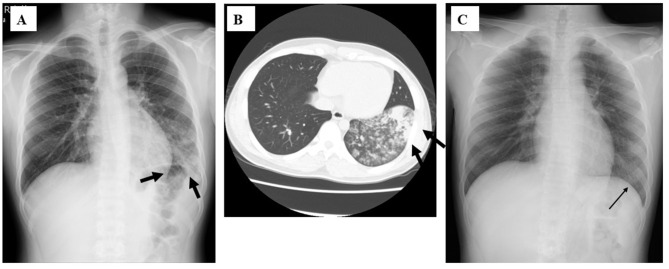

Case series: Four adult cases of M. pneumoniae pneumonia that required admission to the hospital in the 2024-2025 season are presented. Case 1: a 17-year-old male without a specific medical history who was admitted with pneumonia with a severe dry cough. Mycoplasma. pneumoniae genes were detected by multiplex PCR from his sputum. The patient's condition improved with minocycline and corticosteroids for 5 days. Case 2: a 88-year-old man with acute kidney injury who was admitted with severe respiratory failure. Mycoplasma antigen was detected in his pharyngeal swab. He received lascufloxacin drip infusion with corticosteroids for 10 days, and soon improved. Case 3: a 38-year-old woman with maxillary carcinoma and a history of aplastic anemia who was admitted with a severe cough. Mycoplasma antigen was detected in her pharyngeal swab. She received minocycline and corticosteroid drip infusion for 1 week, and finally improved. Case 4: a 74-year-old man with multiple systemic atrophies who was admitted with a severe cough and dyspnea. Mycoplasma antigen was detected from his pharyngeal swab and methicillin-susceptible Staphylococcus aureus (MSSA) was isolated from his sputum. The patient was diagnosed with co-infection with mycoplasma and MSSA. He was treated with sulbactam/ampicillin drip infusion and oral administration of minocycline for 2 weeks, and improved.

Conclusion: All hospitalized adult patients with mycoplasma pneumonia were treated with antibiotics, such as minocycline and fluoroquinolone, along with corticosteroid co-administration, and all of them ultimately improved, although the chest X-ray findings varied. Antibiotics other than macrolides and corticosteroids may be an effective regimen for the treatment of severe mycoplasma pneumonia with potential macrolide resistance.